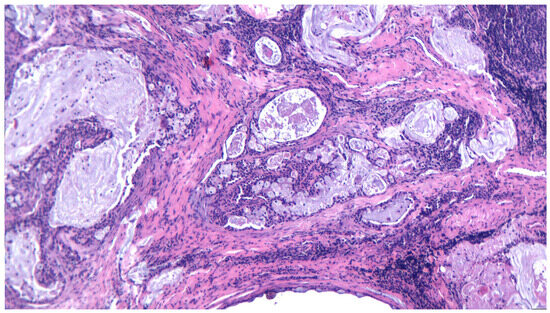

3.2. Pleomorphic Adenoma

3.10. Adenocarcinoma